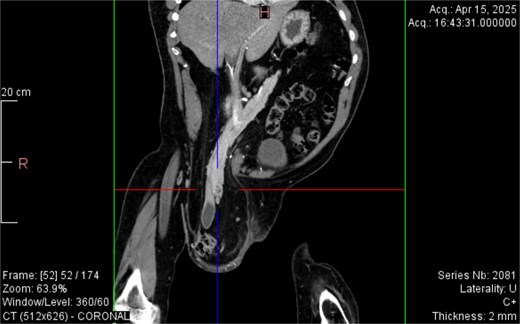

CT imaging (Figs 2–5) revealed a right inguinal hernia containing small bowel loops, ascending colon, the second and third portions of the duodenum, and the pancreatic head. The pancreatic head appeared rotated and displaced inferiorly into the hernia sac, without signs of acute pancreatitis.

Sagittal CT view inguinal hernial sac with pancreatic head and D2 and D3 segment of duodenum.